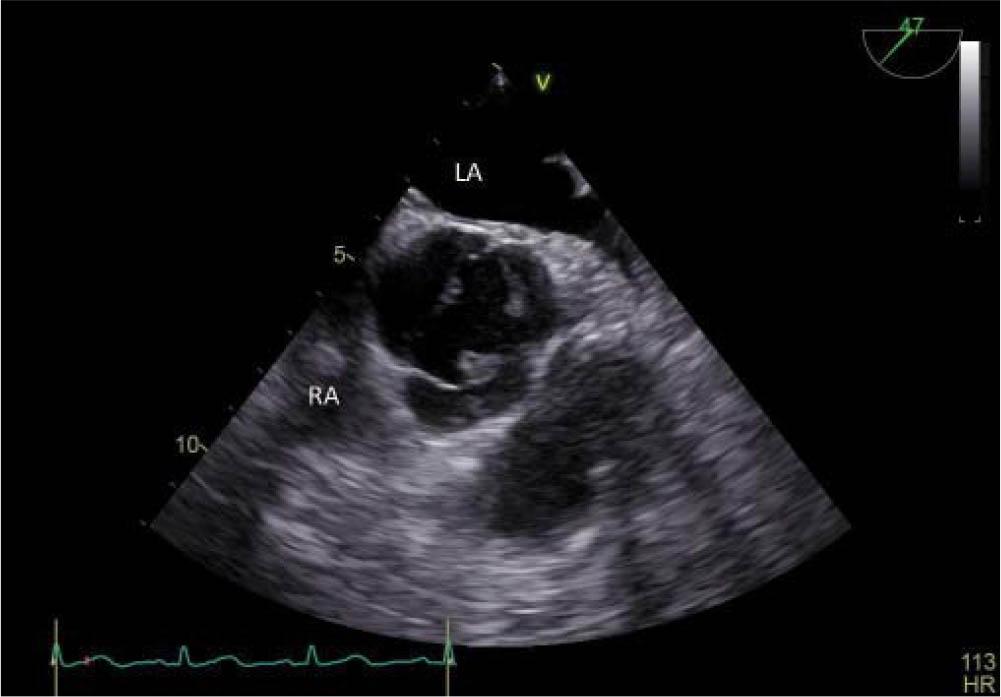

Transthoracic echocardiography (TTE) at admission and afterwards transesophageal echocardiography (TEE), both performed with GE Vivid E9, revealed a hyperechogenic mass, with independent movement, attached to the posterior mitral leaflet, on the atrial surface, with a diameter of 6/6 mm, prolapsing A2 scallop and mild mitral regurgitation (Figure 2). At the same time, it revealed a large mobile mass (diameter 18/4 mm) on the aortic valve, attached to all three leaflets (Figure 3), prolapsing in the left ventricular outflow tract (LVOT) (Figure 4) with high probability of non-coronary cusp (NCC) perforation without hemodynamic impact (Figure 5). Left ventricular size and ejection fraction were normal (Figure 6).

Figure 3

Transesophageal echocardiography – midesophageal aortic short axis view, zoom on the aortic valve- all three leaflets are involved.